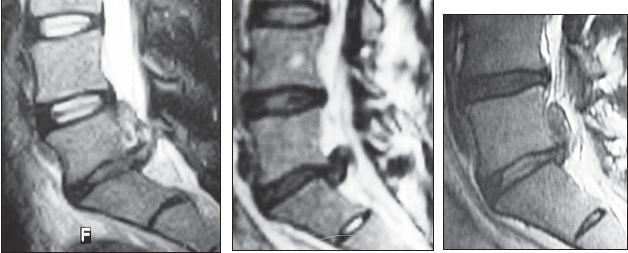

МРТ № 26

На серии МРТ № 26 наблюдаются секвестрированные грыжи межпозвонковых дисков в поясничном отделе позвоночника в сегментах LIV—LV LV—SI с каудальной (каудальной — расположенной ближе к нижней части туловища, направленной вниз) миграцией секвестра (фрагментов межпозвонкового диска)

МРТ № 27

На серии МРТ № 27 наблюдаются секвестрированные грыжи межпозвонковых дисков в поясничном отделе позвоночника в сегментах L]-Sl с краниальной (вверх) миграцией секвестра (фрагментов межпозвонкового диска)